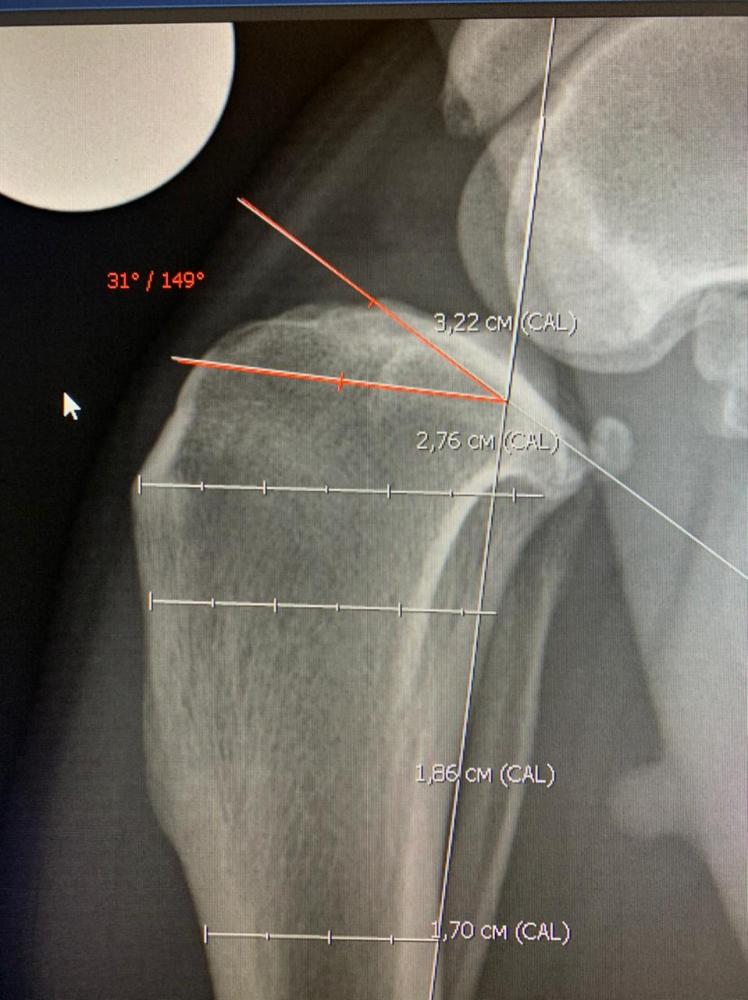

Бэкки Опубликовано 19 февраля, 2021 Опубликовано 19 февраля, 2021 Ну вот мы и дома! Ходит пока на 3 лапках, на лапе, которую оперировали компрессионная повязка, которую не снимать до вс, в воскресенье на приём к хирургу, снимут повязку. Катетер тоже оставили, до завтра, если будет нормально кушать и гулять, завтра снимем. Чувствует себя вроде нормально, покушала и легла спать. Воротник, естественно, жутко не нравится. Пока как-то так. Снимки рентгена: 1 7